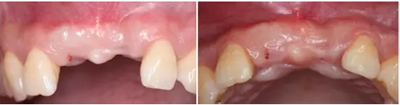

患者33歲,女性,主訴4個(gè)月前因外傷拔除上11、21牙,未行活動(dòng),固定義齒修復(fù),現(xiàn)因影響美觀要求種植修復(fù)。11,21牙缺失,缺牙區(qū)牙齦狀況良好,無潰瘍紅腫,厚齦型,口腔衛(wèi)生較好,無明顯牙齦退縮。

CBCT檢查顯示:水平向骨量不足,無明顯垂直向骨缺損。